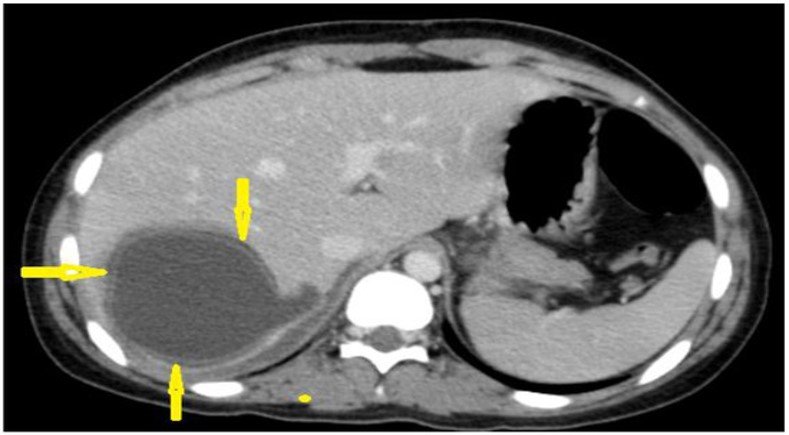

Amoebic Liver Abscess

–Most common liver abscess in India

–Usually solitary, right lobe

–Hypodense lesion with peripheral rim enhancement

–No internal septations

–Clinical fever and RUQ pain

–Anchovy sauce aspirate

Solitary cystic liver lesion with low attenuation center and peripheral thick enhancing wall.

CT Findings are consistent with amebic liver abscess.

Grey scale ultrasound demonstrates 2 round heterogenous hypoechoic lesions.